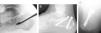

In our experience, osteosynthesis with cannulated screws is preferable because it circumvents the problems usually associated with the use of percutaneous wires, such as loosening, infection, and skin problems. We routinely use a small, 5-mm, lateral incision under the peroneals, through which we insert a forceps, wedge, or fine periostotome to reach the tongue-type fragment. By applying pressure in a proximal direction and flexing the ankle, a good reduction of the subtalar joint is easily achieved. The assistant is prepared to fix the reduction achieved with 2 Kirschner wires, over which we will place the 5-mm or even 6.5-mm cannulated screws. The first screw is inserted in an anterolateral direction from the internal aspect of the Achilles tendon and runs under the subtalar joint to the anterior process of the calcaneus. It supports the anterolateral and anteromedial fragments, thereby keeping the tongue-type fragment from collapsing. The second screw is placed in a posteromedial direction from the external aspect of the Achilles in an attempt to stabilize the superolateral tongue-type fragment with the posterior fragment. Post-operative immobilization generally is not required, and progressive weight-bearing is permitted from the fourth week (Fig. 2).

Tongue-type fracture treated with closed reduction and percutaneous fixation. (A) Percutaneous reduction through a very small lateral incision for using a wedge to raise the tongue-type fragment. (B) Follow-up lateral x-ray showing the reduction achieved and fixation with 2 6.5-mm cannulated screws in anterolateral and posteromedial orientation. (C) Axial view of the same case.